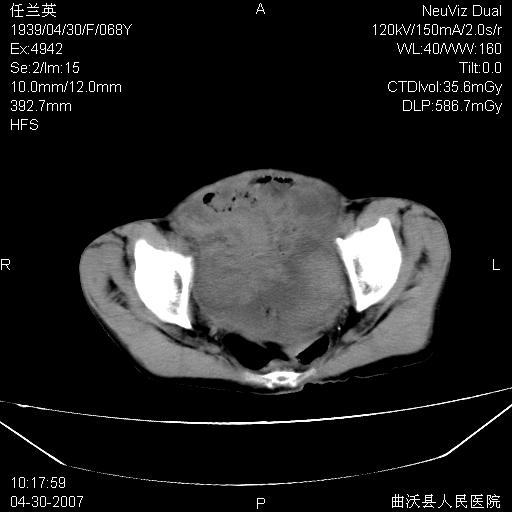

患者,女,68岁,感觉腹部憋涨发硬数天,查b超发现左盆腔有囊性肿物和少量腹水,行ct检查

1.考虑卵巢肿瘤并腹腔广泛性转移可能性大;

2.腹盆腔少量积液。

支持左侧卵巢恶性肿瘤伴网膜、腹膜广泛转移。

难的一见 典型 - 网膜饼  冰冻骨盆 可以当教学片了